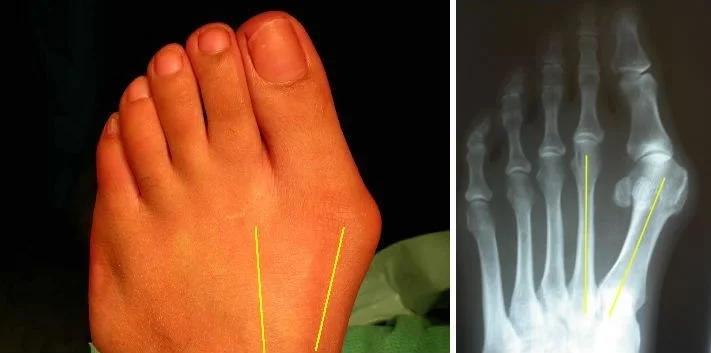

Hallux Valgus

- Definition: lateral deviation of the great toe (hallux) and medial deviation of the first metatarsal

Radiology - Hallux Valgus

- XR views:

- AP standing:

- Lateral deviation of big toe

- Increased varus of 1st MT

- Subluxation of MT-Phal. joint